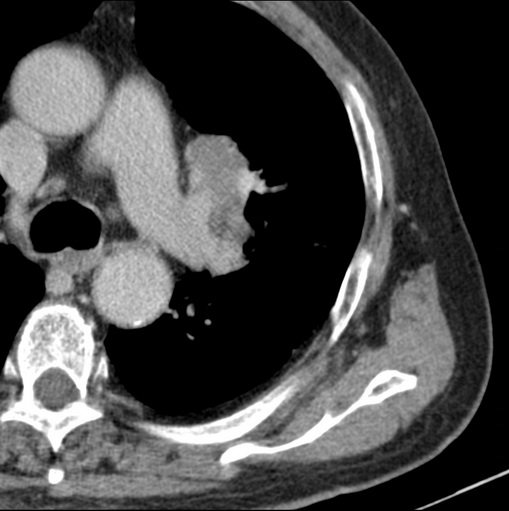

标题: CT25434:胸部CT增强扫描

男性患者 81岁 咳嗽 咳痰 咯血

肿块贴近左肺门,包绕左上肺动脉,形态不规则。肿块增强扫描中度强化。纵膈内主动脉弓左旁间隙、气管隆突前、下间隙见多枚淋巴结影。综上考虑左侧中央型肺癌可能性大。图片没有完整上传,尤其是左肺上叶支气管分支层面没有上传,因此不好判断是叶支气管中断还是段支气管中断。另外,下图红色部分所示是“黏液支气管征”吗?